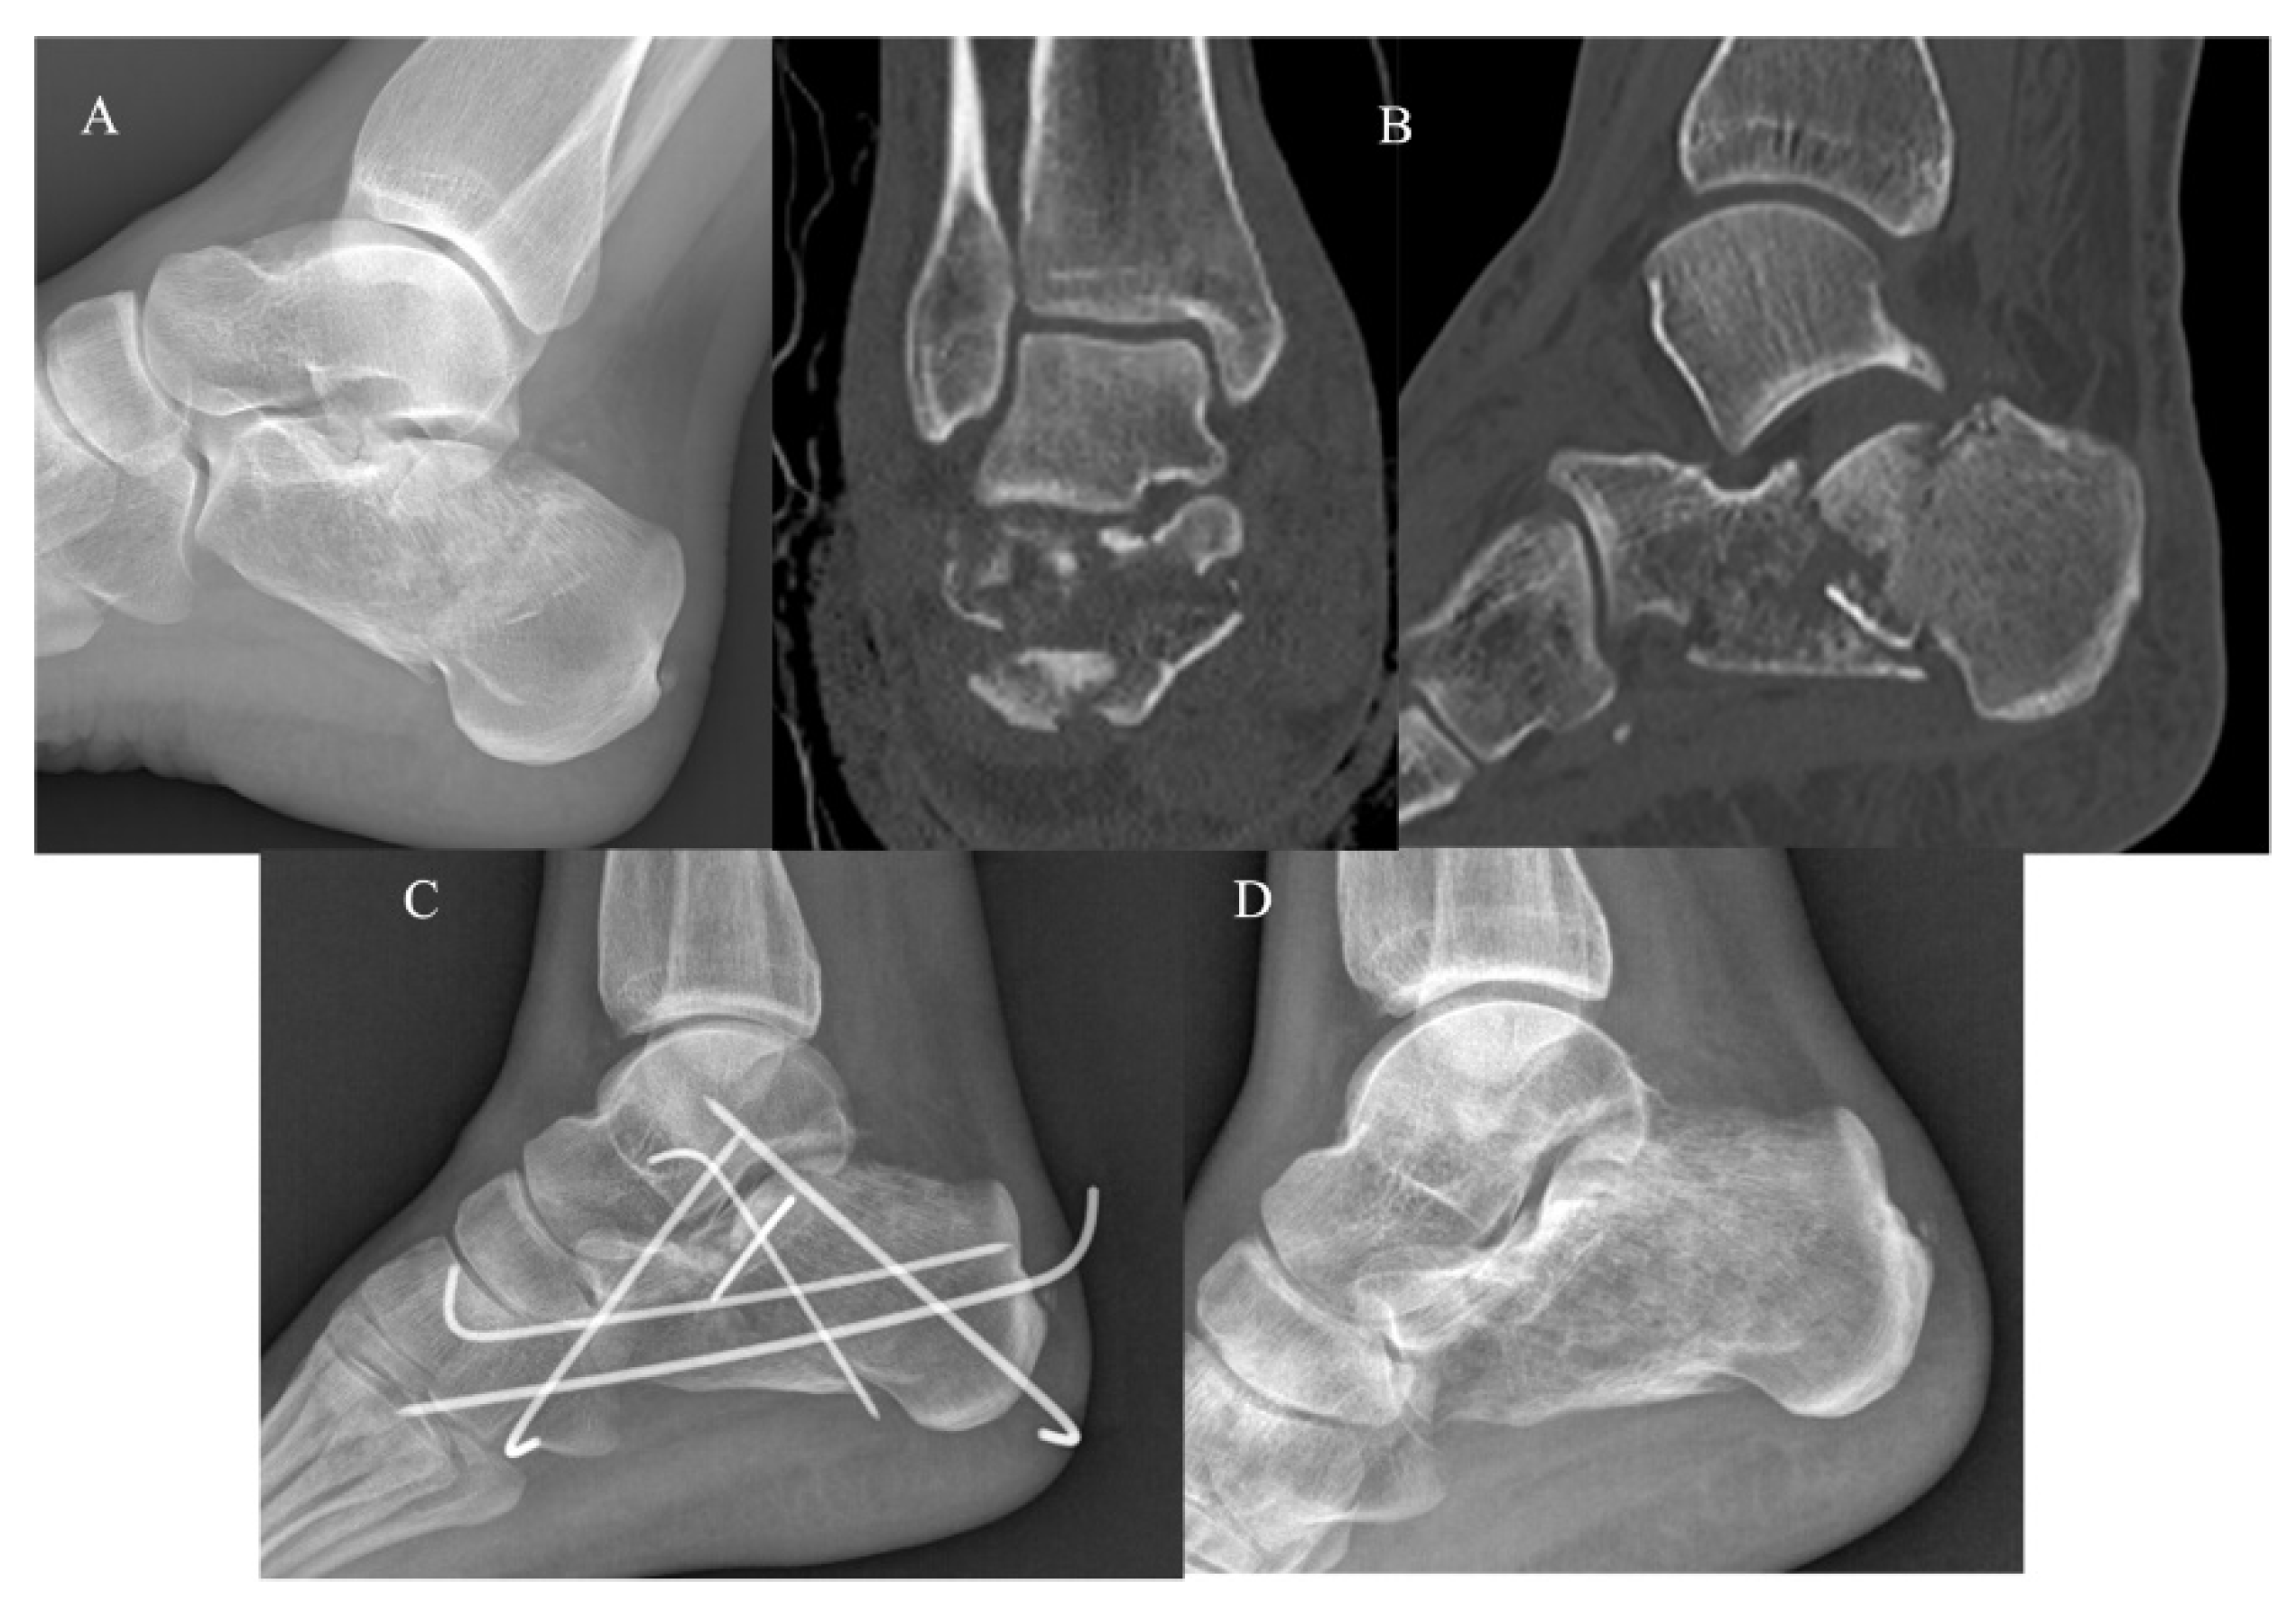

The KG (Figure 2) and PG (Figure 3) consisted of 20 and 22 CF, respectively. The group demographic characteristics and specific mean final follow-up are summarized in Table 1.

Figure 3.

Extended approach and dedicated plate. (A) Pre-operative radiographs; (B) pre-operative CT scan in coronal and sagittal plane showing a Sanders III CF; (C) post-operative radiographs at 4-year follow-up.